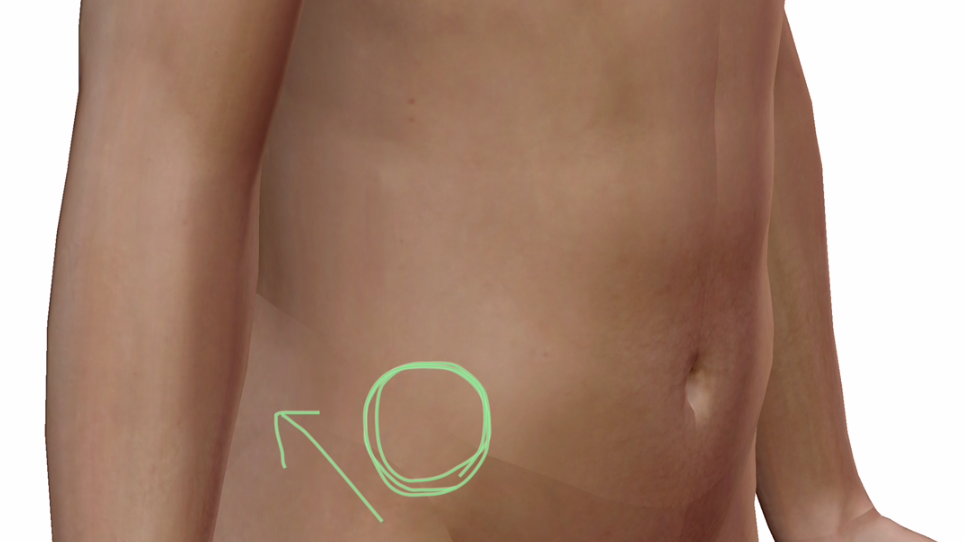

これを上向きで寝てるところで、↓

この緑矢印の方向に押します。

そうすると、痛みが取れます。

上前腸骨棘から動きの渋くなっている仙腸関節を動かすと、痛みが取れやすいです。